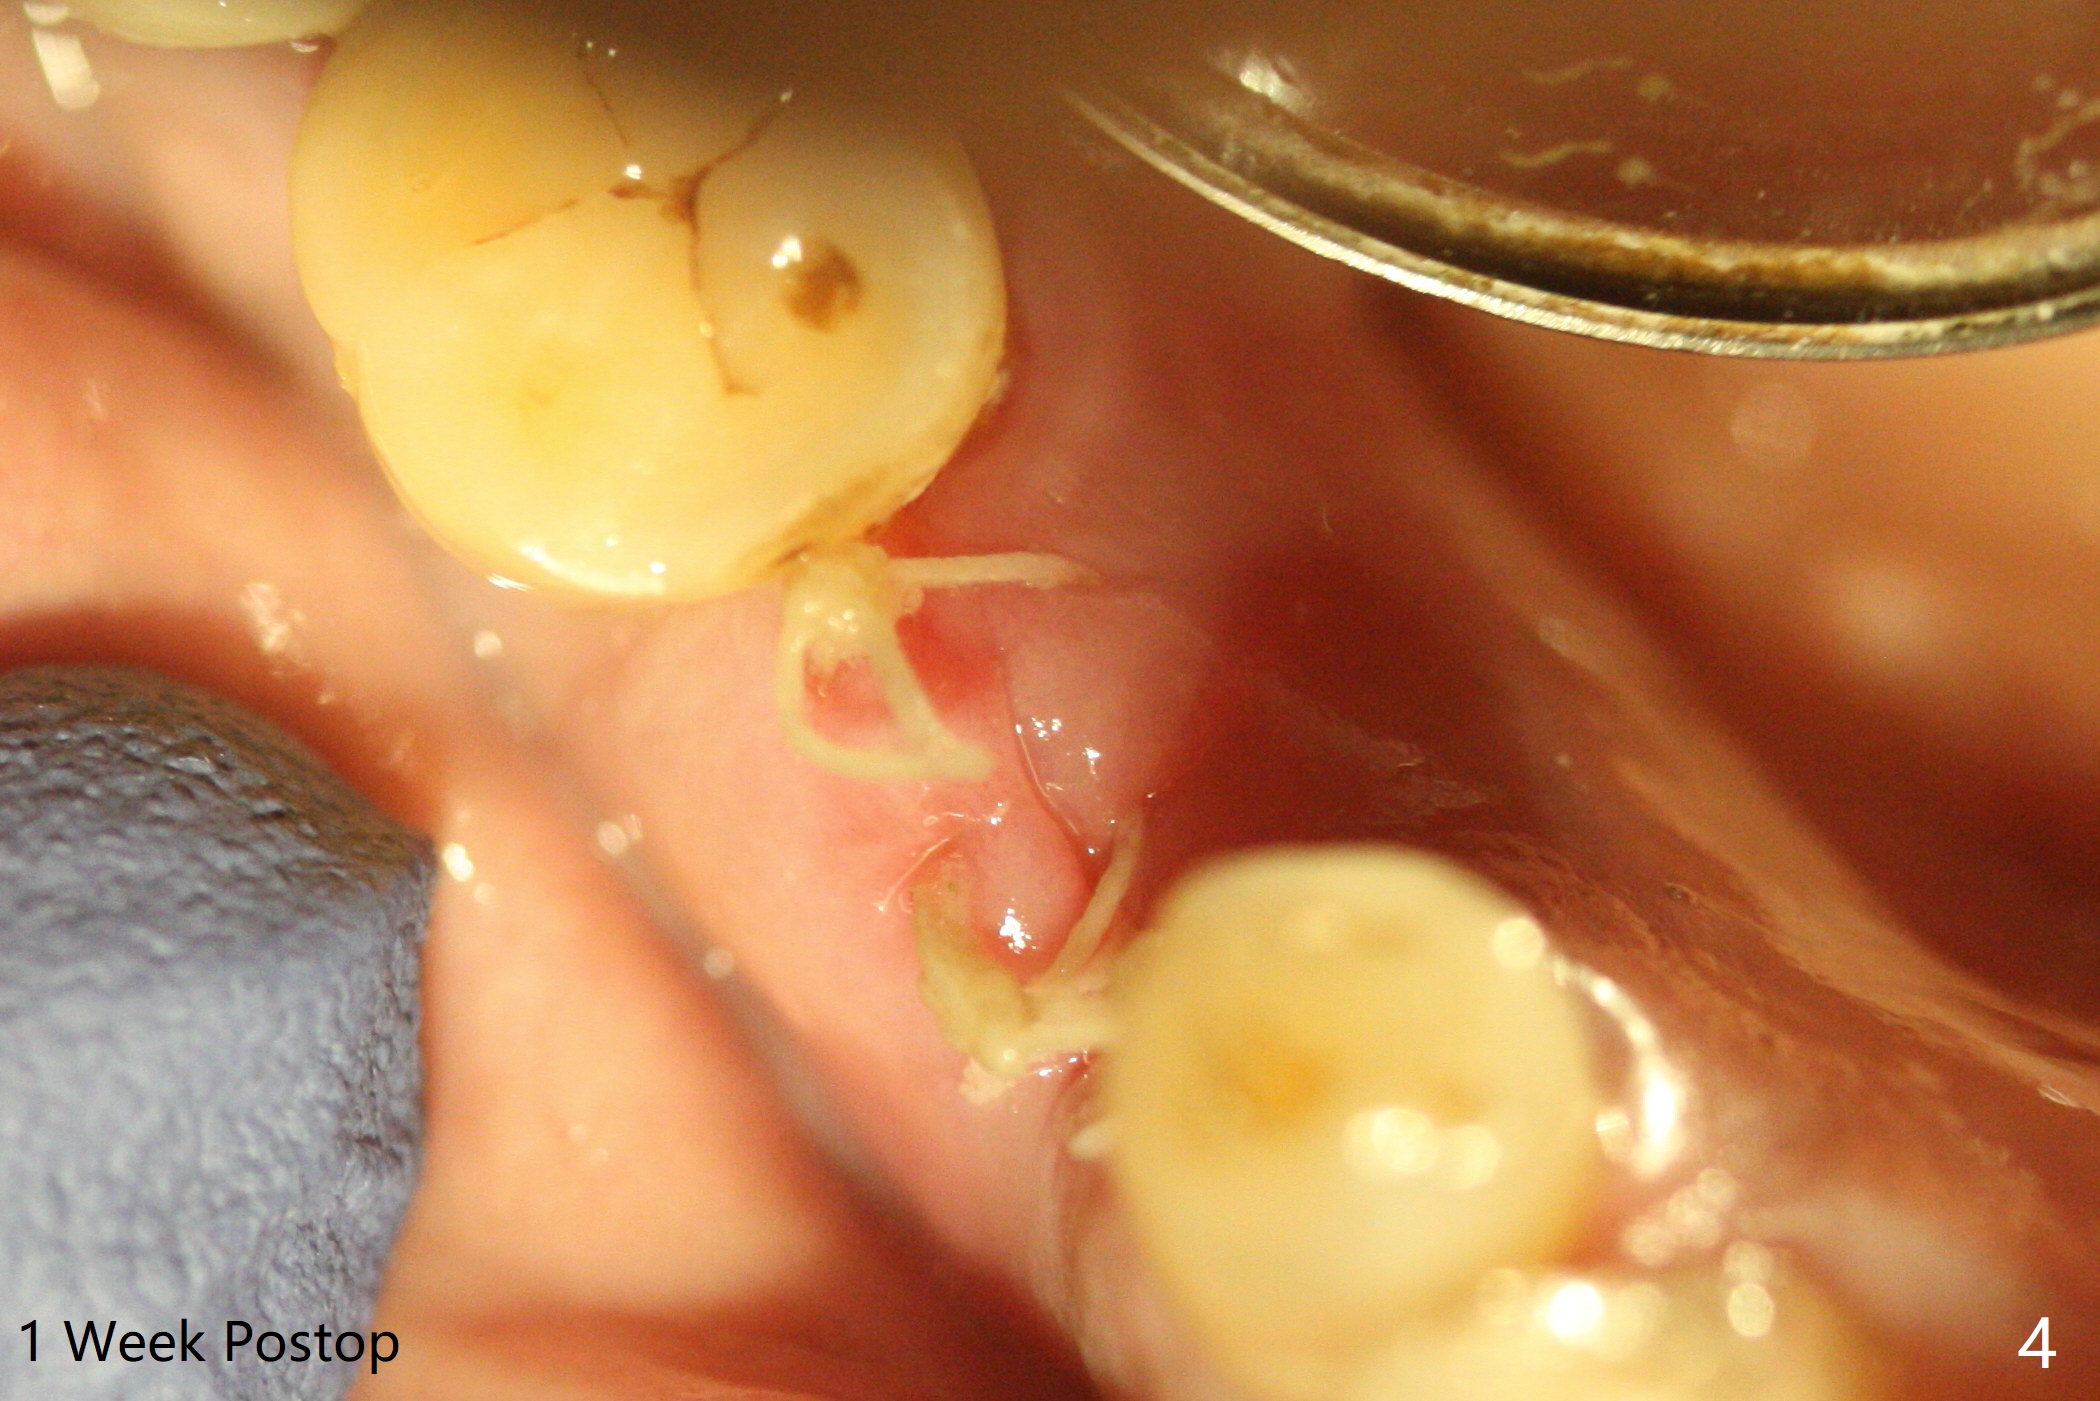

A 77-year-old woman agrees to have the lower right 2nd premolar extracted after lengthy delay (Fig.1,2 buccolingual plate present, but low) and grafted (Fig.3 *).  Cortical graft is heavily packed, covered by a small piece of 6-month membrane and sutured with 4-0 Chromic gut suture.  The socket is closed 7 days postop (Fig.4).   The buccal plate seems to have been reformed 6 months postop (Fig.5,7, as compared to Fig.6 (pre-fracture)).  Return to No Deviation Surgery  Xin Wei, DDS, PhD, MS 1st edition 08/19/2020, last revision 05/12/2021